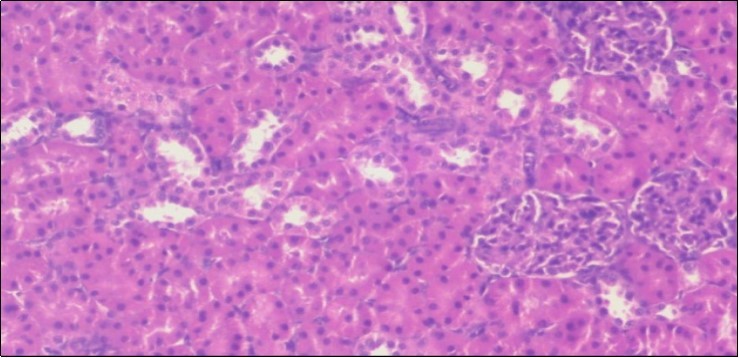

The histological examination of the kidney of the control rats fed on a standard diet showing normal rounded capsules with normal Bowman's glomeruli, round proximal tubules and elongated distal tubules with high cuboidal cells figure 1. The rats fed (HFD) showed fatty degeneration of the tubules with eosinophilic material deposition, glomerular atrophy with wide urinary space and distal tubules with extrusion of nuclei into lumen figure 2. By comparison kidneys of rats which were treated by fennel after being obese and the control rats observed partial improvement in both Bowman's capsules and proximal tubules. Note the distal tubules show less focal fatty infiltration figure 3.While examination of rats kidney that were treated by ator after obesity showed improvement in Bowman's capsules with normal glomerular and partial improvement in proximal tubules and distal tubules, figure 4. Kidney of rats that were treated by fennel and ator after obesity and the control rats showed high improvement in the tissues with normal glomerular and that Most of Bowman's capsules and renal tubules, restoring their normal appearance figure 5.

Figure 4.Photomicrogragh of kidney section of treated rat with Ator drug showing improvement in Bowman's capsules with normal glomerular and partial improvement in proximal tubules and distal tubules, (H&E) (40X).